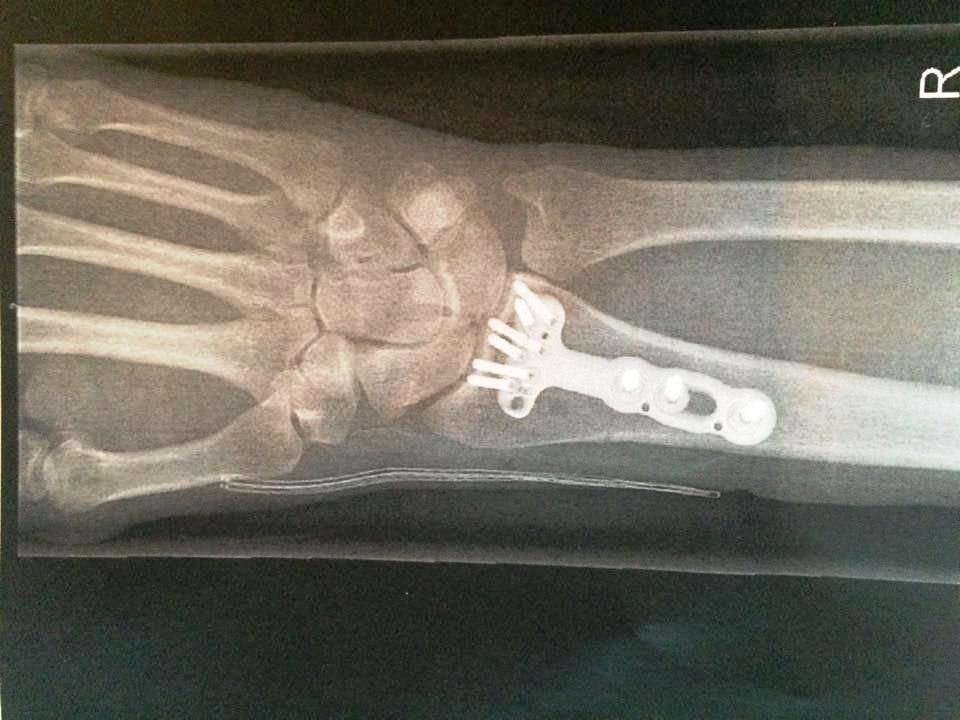

Operatøren, det er visst det de kaller kirurgene sine for tiden, kom innom. - Er du fornøyd?, spurte jeg. Han var det. Han hadde fått samlet bruddstykkene og skrudd dem til en plate, sydd igjen og lagt på kompress. Ingen gips. Gud så praktisk.

- Den plata er nok. Ta stingene hos fastlegen om fjorten dager og kom til kontroll hos meg tidlig i juni. - Når Kan jeg sykle igjen? Hold deg på rulla først, ikke belast bruddet før du har vært hos meg (ah, det er åpent for tolkning, tenkte jeg). - Skal den plata ut igjen? - Nei, den tar du med deg i graven.